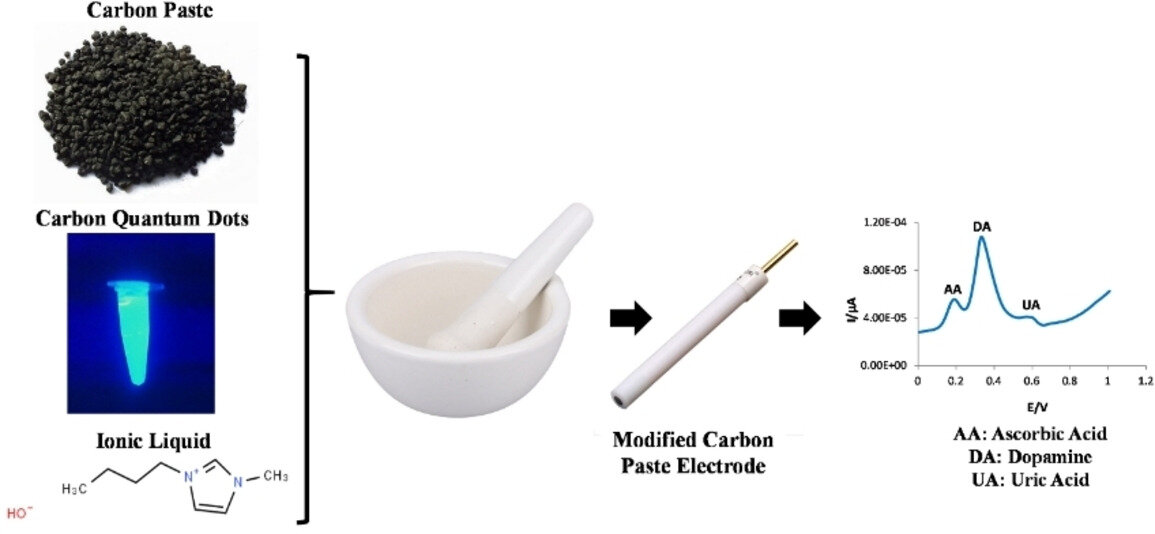

A new test that measures dopamine levels in biological fluids could help with the detection of depression, Parkinson's disease, and other disordered marked by abnormal dopamine levels.

Use of 3D Printing Techniques to Fabricate Implantable Microelectrodes for Electrochemical Detection of Biomarkers in the Early Diagnosis of Cardiovascular and Neurodegenerative Diseases

Could a new test that detects dopamine levels help diagnose neurological diseases?

New dopamine sensor could help detect brain disorders rapidly